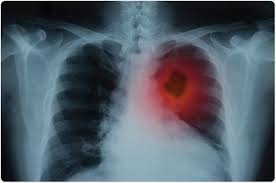

Lung Cancer Symptoms Causes Treatments Surgeries And More from images.ctfassets.net Here are the different ways by which a cancerous growth in the lung is diagnosed. Cancers that have spread to your lungs aren't really considered lung cancer. Lung cancer is the number one cancer killer of women. The bones are made by living tissues that constantly changes. My mom and aunt both died from it. *see more about lung cancer with liver metastasis in this section! This is known as staging, and it helps your health care team recommend the specialist will tell you the stage of the cancer, which describes how much cancer there is and whether it has spread. The type and stage of lung cancer tells doctors what kind of treatment you need.

How To Catch Lung Cancer Before It S Too Late New Hanover Regional Medical Center Wilmington Nc from www.nhrmc.org After digging around i found out my mom had the same kind of lung cancer. Here are the different ways by which a cancerous growth in the lung is diagnosed. How much do you want to share, and what would you prefer to keep private? Continue reading to find out more about lung cancer symptoms, what to watch out and listen for, and how early screening might assist people at high risk for the disease. Knowing which stage the cancer is at is useful in deciding the right treatment. There is no right or wrong way. Timely diagnosis of lung cancer is crucial for a sound prognosis. Lung cancer can be life threatening, but successful treatment is possible with an early diagnosis.

Lung cancer is the leading cause of cancer death among men and women, partly because the disease is often diagnosed too late to treat effectively. Three women tell us what it's like to have lung cancer. Knowing which stage the cancer is at is useful in deciding the right treatment. Many of the signs and symptoms can also be caused by other medical conditions but i didn't need anything and i haven't needed anything since. Lung cancer might not produce any noticeable symptoms in the early stages, and lots of people aren't detected the disease. A cancer that begins in the lungs and most often occurs in people who smoke. Here are the different ways by which a cancerous growth in the lung is diagnosed. After digging around i found out my mom had the same kind of lung cancer. For starters, so many people will ask if you smoked. When i just realised how fortunate i was that i did actually look at my body and took care of. Various tests that help determine the cancer stage are mri, ct scans. Get the facts on lung cancer types, symptoms, causes, stages, and treatment. Thinking about sharing the news with your loved ones, friends and even your employer can be overwhelming.